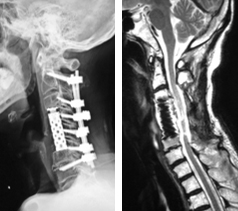

頚椎後方除圧固定術

対象となる疾患:頚椎症性脊髄症、頚椎後縦靭帯骨化症、頚椎椎間板ヘルニア、脊椎腫瘍など

頚椎後方除圧固定術は、頚椎の後方からアプローチして、圧迫因子となっている骨や靭帯を削除したり、金属製のスクリューなどで頚椎を固定する手術法です。頚椎に不安定性があったり、後弯と言って骨の並びが後ろに弯曲している場合などで有効な手術法となります。通常、手術翌日より座位や歩行訓練を行います。術後は、頚部を固定する装具を約1−3カ月装着します。

手術前のCTおよびMRIでは、椎体の後ろにある骨化した後縦靭帯が脊柱管内に大きく占拠し、脊髄を強く圧迫しています。

前方から椎体切除および骨化巣の浮上術を行い、代わりに金属製のケージを設置しました。非常に高度な狭窄であったため、後方からも除圧を追加し、頚椎のカーブを維持するためにスクリューとロッドによる固定を行いました。術後、神経症状は著明に改善しています。